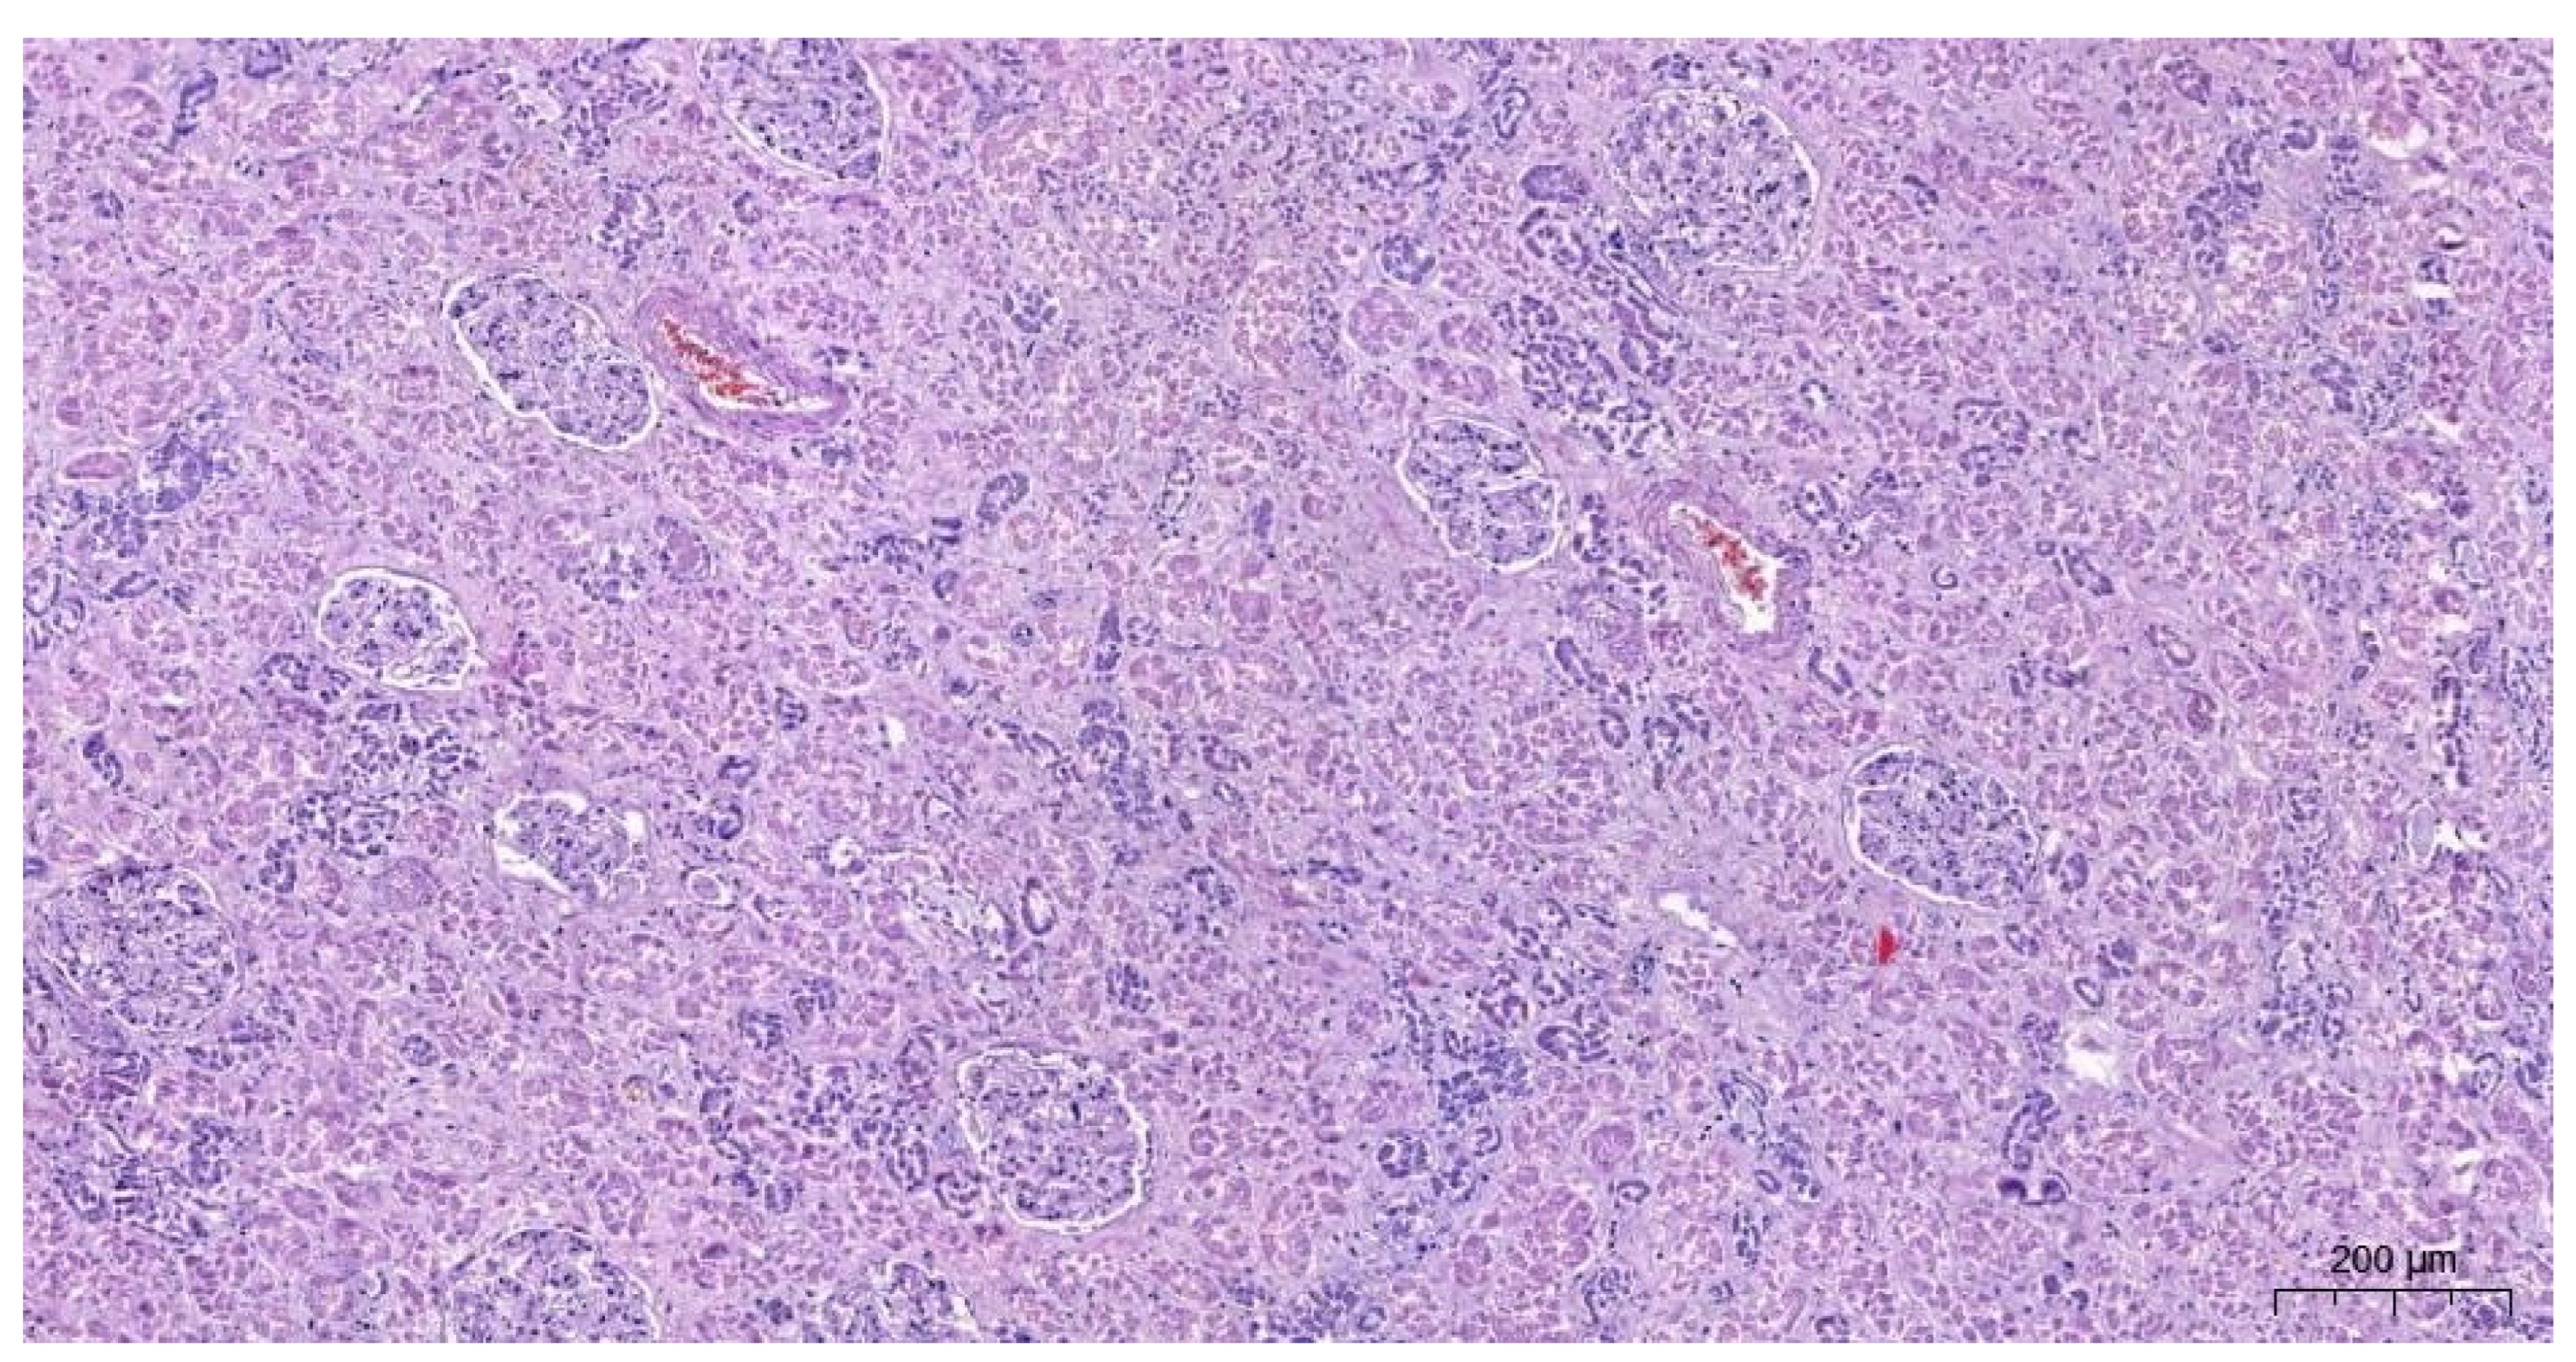

2.2.3. The Microscopic Examinations